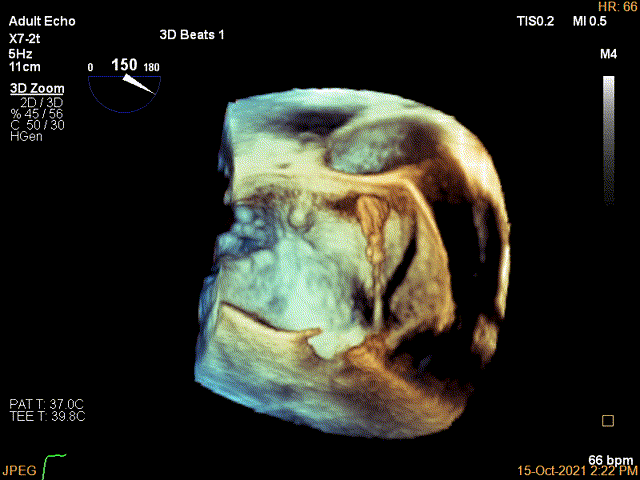

3D视图下开夹子并调Rotate

X-plane:下夹子尝试先捕获1区脱垂瓣叶

3D证实夹子内侧残余Flail

3D视图两个夹子近似并排排列,排列很紧密